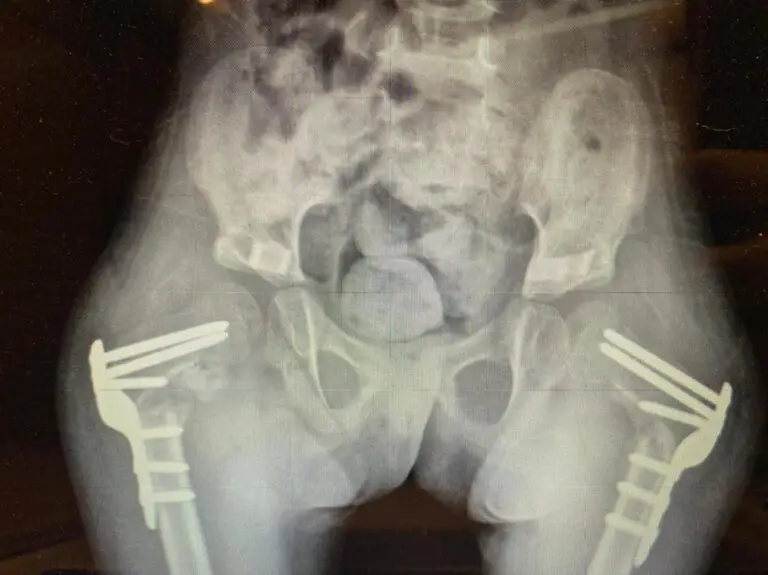

Com o tempo, isso pode levar a encurtamentos, subluxações e até luxação do quadril, comprometendo a função motora e causando dor.

Quando falamos de crianças com PC, estamos lidando com movimentos atípicos, padrões espásticos e restrições articulares que exigem um olhar clínico diferenciado.